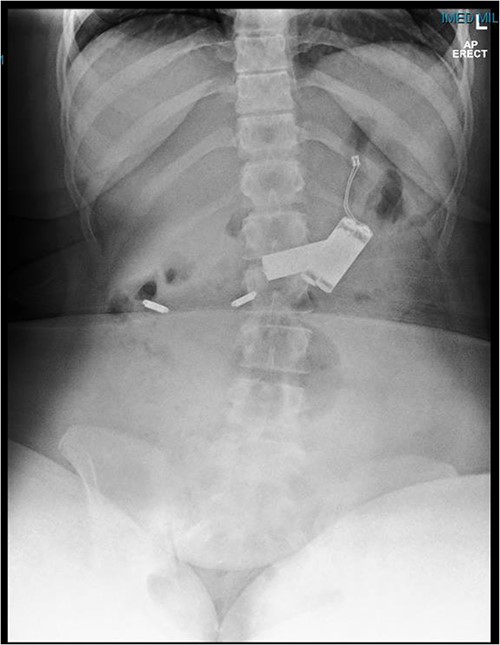

This is a case of a 12-year-old Caucasian female with a background history of autism spectrum disorder presented to the emergency department of a rural hospital in Australia after the ingestion of two NiMH batteries. This is the third presentation of battery ingestion in 2 weeks. She was asymptomatic and did not complain of abdominal pain at the time of review. On examination, she had a soft abdomen with mild epigastric tenderness and guarding. Abdominal radiograph showed the presence of two battery structures projecting to the left of the upper abdominal area overlying L1/2 discs (Fig. 1). To the right of L2, there are two other round devices resembling metallic-type foreign bodies. A gastroscopy was performed 3 hours after her presentation. The gastroscopy revealed extensive superficial erosion to the antral and greater curvature (Fig. 2). Two NiMH batteries were retrieved. However, the other two smaller foreign bodies have passed the jejunum proximally and were unable to be retrieved. She was discharged home on sucralfate, pantoprazole and ColonLYTELY to promote passage of the remaining foreign bodies. Abdominal X-ray was repeated after 1 week, which showed no further foreign objects retained in the patient’s body. She recovered uneventfully with no development of any residual symptoms.

Abdominal X-ray demonstrating four battery-shaped foreign body at the level of L1/L2.